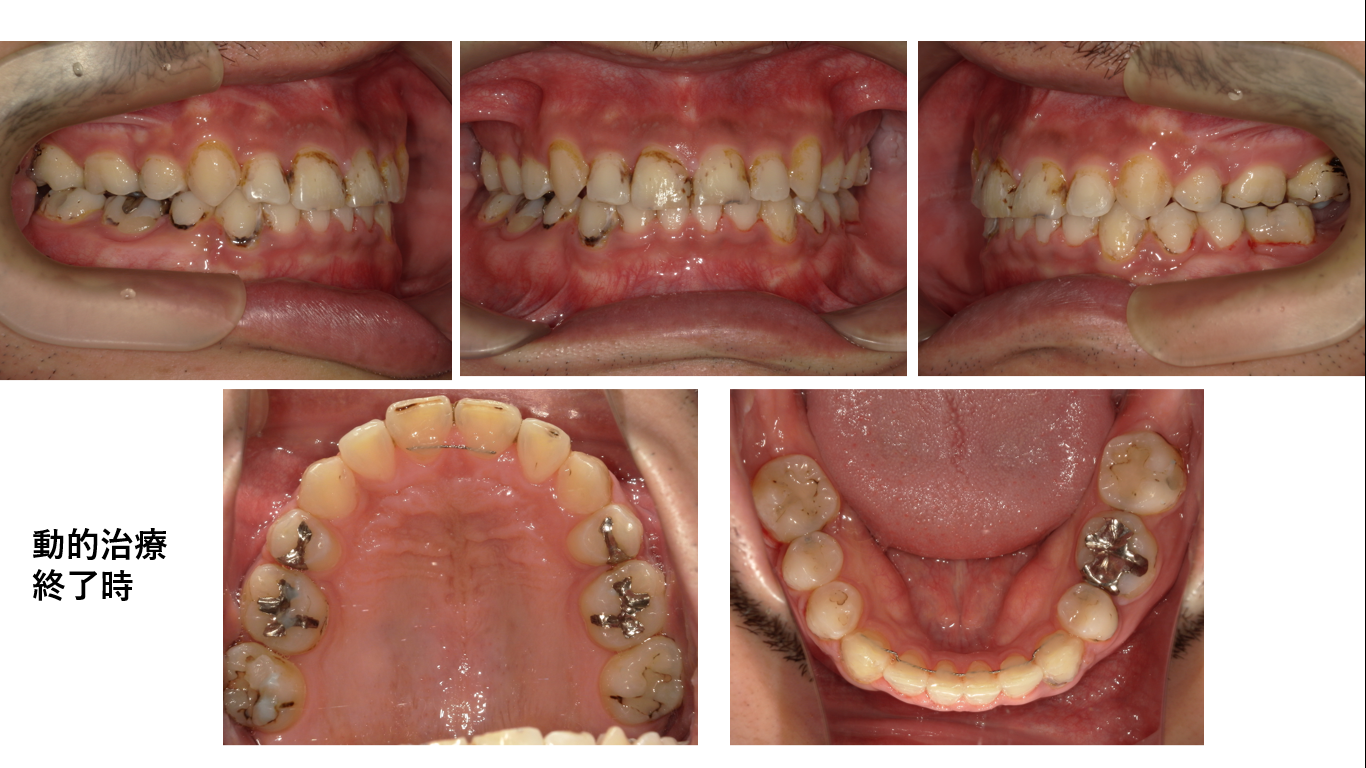

矯正症例146 骨格性下顎前突、八重歯、変則抜歯症例

初診時34歳男性、治療期間3年4か月、抜歯部位:上顎週左右4番、下顎右側4番、下顎左側6番、8番。治療費総額124万円(税込み)

左の6番は根幹治療がしてあり根尖病巣を確認できたので抜歯となりました。

下顎が左右で非対称な並びとなっています。並んでいる歯の種類が違うからです。これも仕方がないことで時々あります。